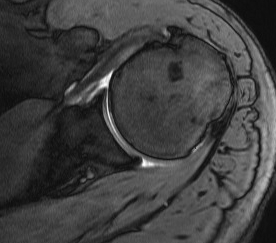

MRI

Inflammation and thickening of the rotator cuff tendons

Mild inflammation of the supraspinatus tendon insertion

Thickening and edema of the supraspinatus and infraspinatus tendon

Subscapularis tendinosis